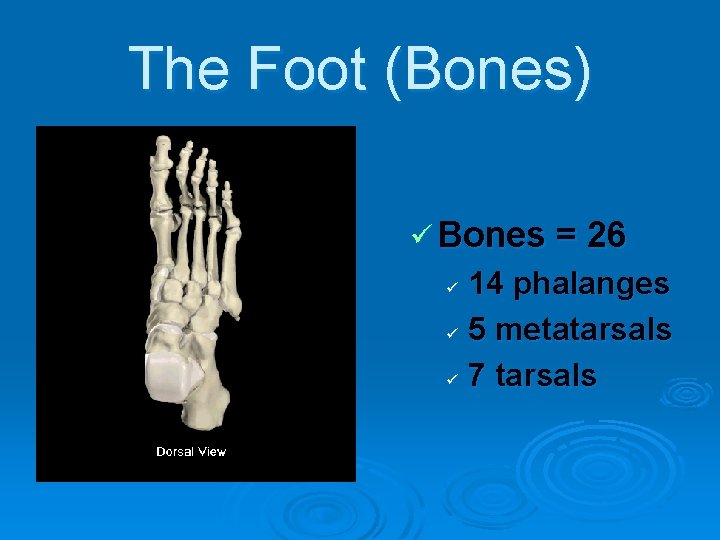

The Foot (Bones) ü Bones = 26 14 phalanges ü 5 metatarsals ü 7 tarsals ü